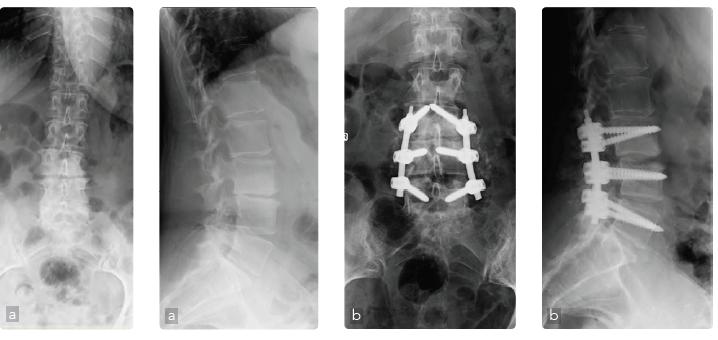

Caso 1: Spondilolistesi L4-L5 degenerativa

Maschio, 79 anni, spondilolistesi L4-L5 (cardiopatico 4 bypass). Operato 25 anni prima di discectomia L5-S1. Lombosciatalgia cronica aggravatasi negli ultimi 6 mesi e cluadicatio vertebrale con iniziale riduzione della forza. Il quadro radiografico e la risonanza mostrano una stenosi del canale a 2 livelli e la spondilolistesi L4-L5 (a). Operato di decompressione, riduzione dell’olistesi, artrodesi intersomatica e posterolaterale strumentata L3-L5 (b). Ottimo recupero funzionale a 4 mesi.